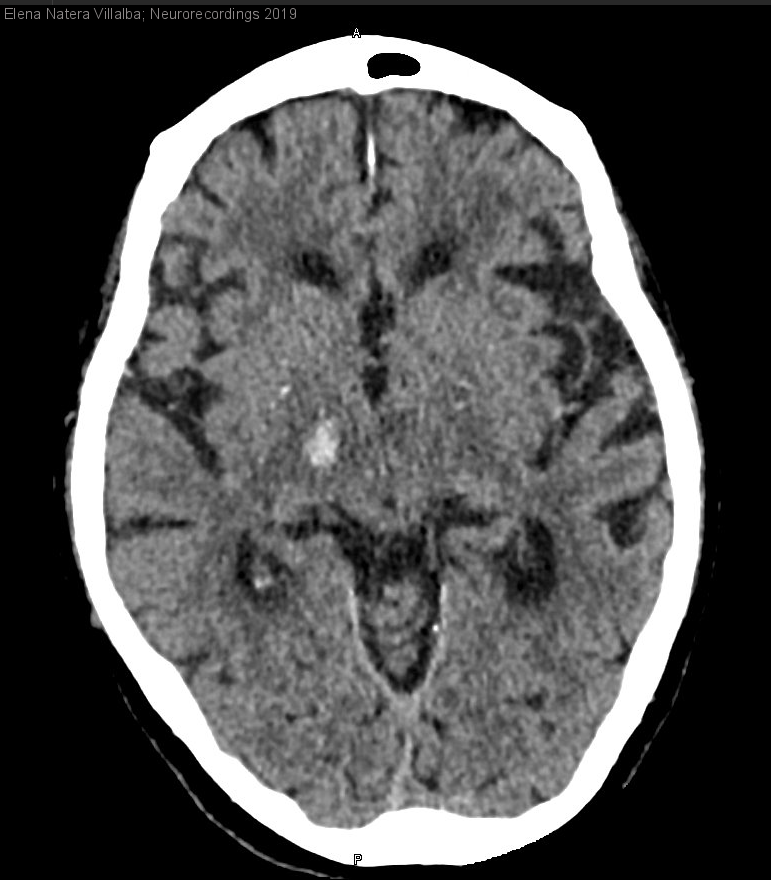

Diagnóstico final: Hemicorea izquierdo de inicio agudo secundaria a hematoma talámico derecho de probable etiología hipertensiva

Mujer de 91 años hipertensa, dislipémica, independiente y sin deterioro cognitivo, en tratamiento con ácido acetilsalicílico (prevención primaria), que acudió a Urgencias por un cuadro de 24 horas de evolución de sensación de descoordinación en extremidades...